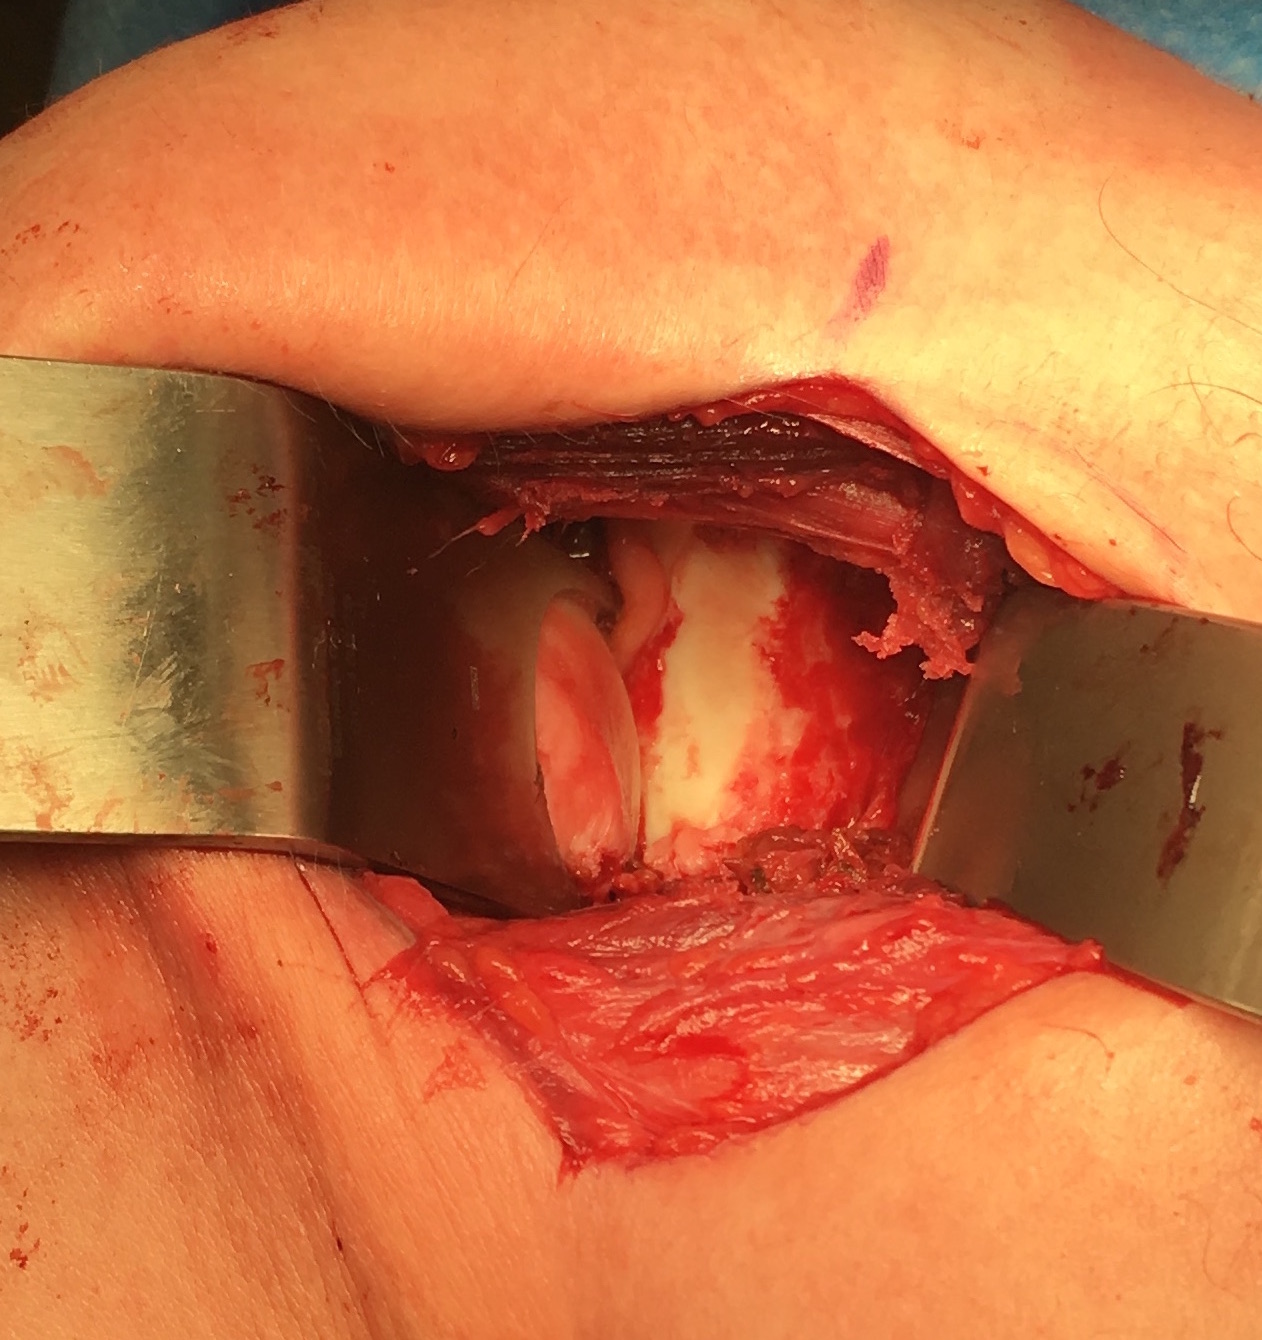

Case 1: Failed Latarjet

![]()